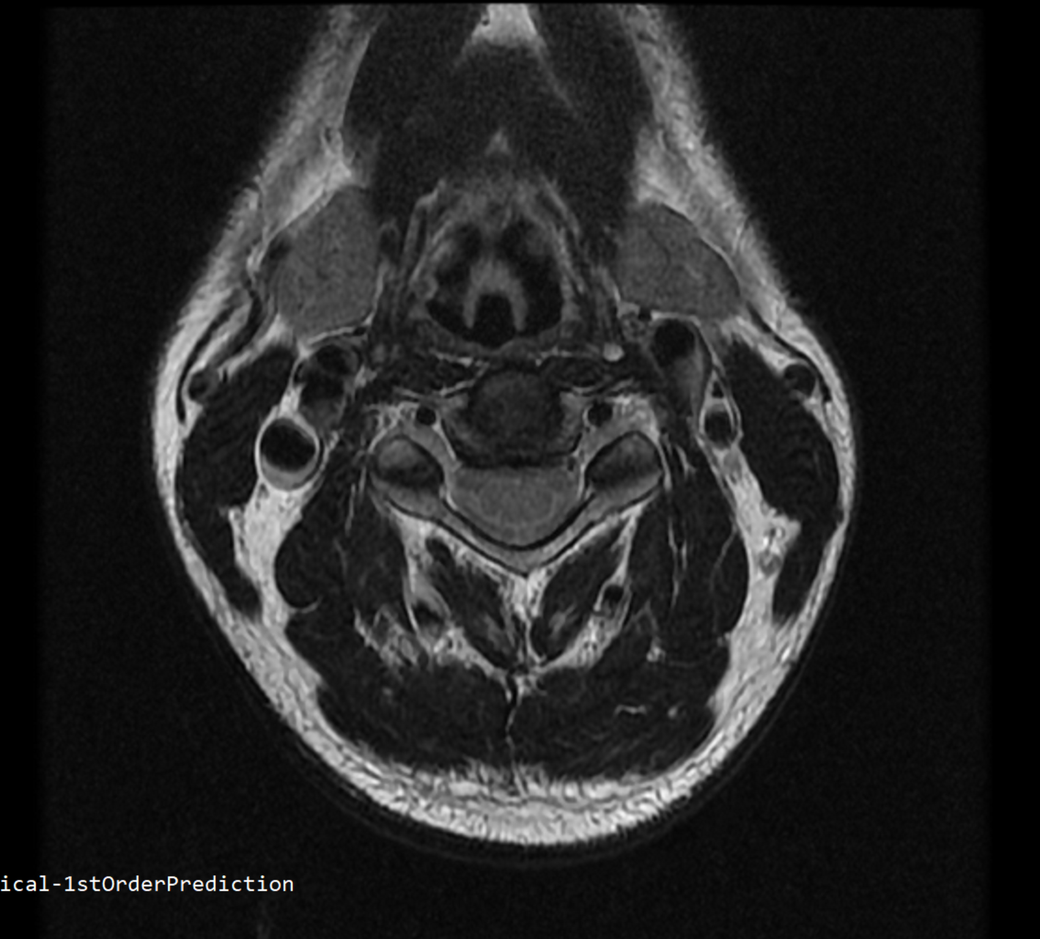

안녕하세요 목 경추 상단부터 순서대로 mri 촬영인데요

전체적으로 봐주시면 감사하겠습니다

• 2번 째 사진